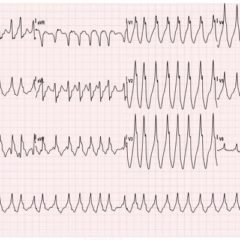

Elbow dislocations are classified by the position of the radio-ulnar joint relative to the humerus.1 Images 1, 2, and 3 show a left posterior elbow dislocation; the radius and ulna are displaced posteriorly with respect to the distal humerus. The lateral view of the elbow most clearly shows this: trochlear notch of the ulna is empty and displaced posteriorly relative to the trochlea. There is no associated fracture. Images 4 and 5 show the elbow status-post reduction, demonstrating proper alignment of the distal humerus with the radius and ulna.

Posterior elbow dislocations should be reduced as soon as possible.1 Patients should receive adequate sedation and/or analgesia. One method of reduction is the “puller” technique, during which a practitioner stabilizes the humerus, while a second practitioner applies force against the anterior forearm, with gentle traction distally.1 Post-reduction neurovascular reassessment is important. After successful reduction, patients can be immobilized in a posterior long arm splint.